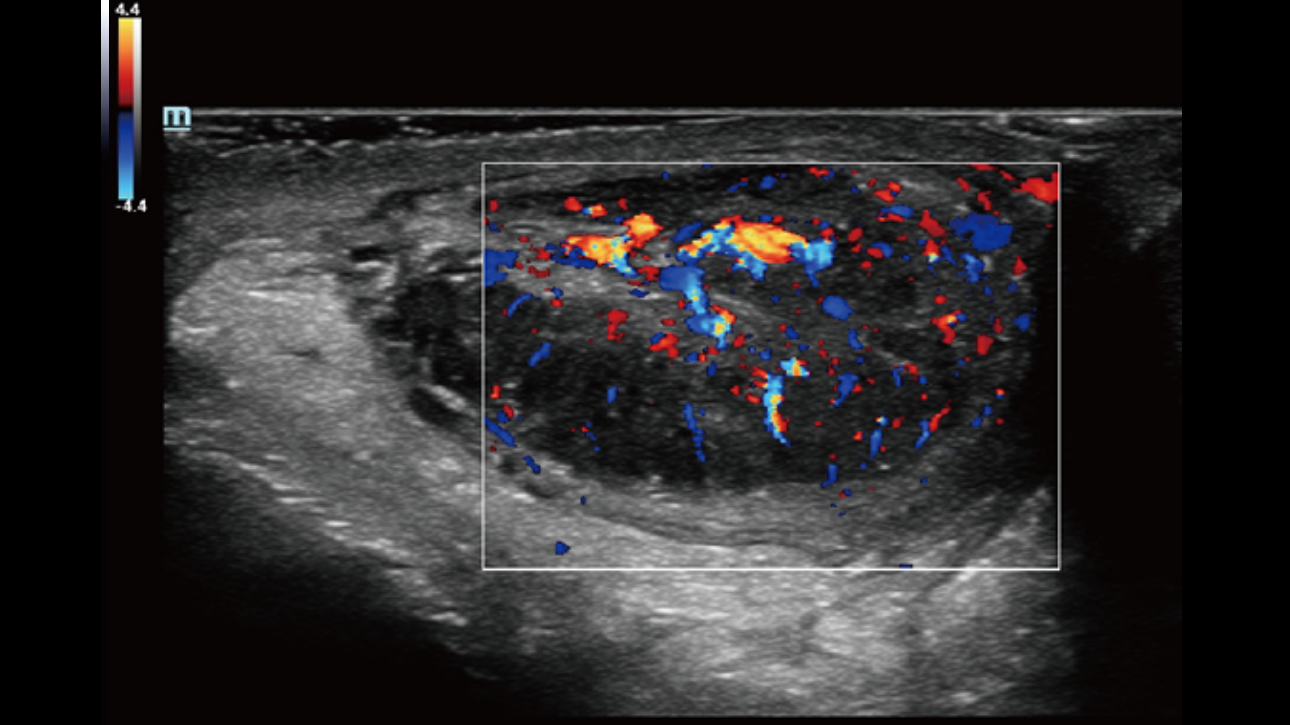

The channel data based ZST+ is an extraordinary innovation, representing an ultrasound evolution. Transforming ultrasound metrics from conventional beamforming to channel data based processing; ZST+ is able to deliver multiple imaging advances: Advanced Acoustic Acquisition, Dynamic Pixel Focusing, Sound Speed Compensation, Enhanced Channel Data Processing and Total Recall Imaging.

By transmitting and receiving a relatively smaller number of large zones, Advanced Acoustic Acquisition extracts more information from each acquisition, 10 times faster than a conventional line-by-line beamforming method.

Dynamic Pixel Focusing technology allows the Resona 6 to achieve extreme uniformity in pixel level throughout the whole field of view. Now there's no need to adjust the focal positions to achieve uniformity across patient exams.

Channel data based ZST+ provides Enhanced Channel Data Processing for greatly improved imaging clarity. By multiple and retrospective channel data processing, it makes the best use of acoustic information for image improvement.